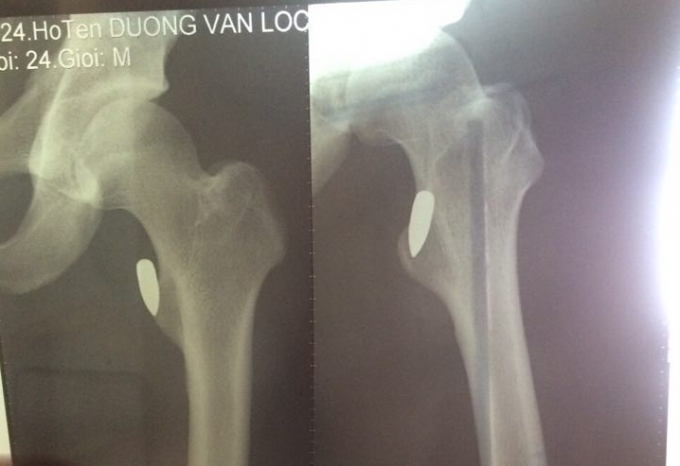

Bác sĩ tại Bệnh viện Lạc Việt (Vĩnh Phúc) cho biết, kết quả phim chụp X-quang cho thấy anh Lộc bị trúng đạn, rất may đầu đạn chỉ đi vào phần mềm, còn cách xương chỉ vài milimét.

Vì vết thương khá phức tạp nên sau khi sơ cứu, anh Lộc được chuyển xuống viện Bạch Mai rồi chuyển sang Việt Đức để mổ gắp đầu đạn ra ngoài.

Tuy nhiên, đến giờ các bác sĩ vẫn chưa thể mổ để gắp đầu đạn, vì tổn thương do đạn bắn gây ra khá nghiêm trọng, đầu đạn nằm sâu, gần xương nên chưa thể can thiệp ngay.